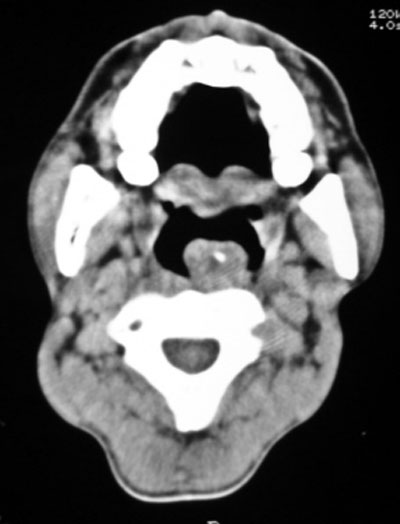

以下是引用随光逐影在2009-4-23 19:35:00的发言:[br]1)鼻咽、口咽、左侧鼻腔及右侧鼻后孔处新生物,考虑息肉可能性大。2)双侧上颌窦及双侧筛窦炎症,不排除双侧上颌窦内息肉可能。

以下是引用syfszcw在2009-4-23 13:21:00的发言:[br]双侧上颌窦 筛窦慢性炎症,鼻息肉 会厌ca[br][br][本贴已被 syfszcw 于 2009-4-23 13:36:46 修改过]

以下是引用bmw011在2009-4-23 13:23:00的发言:[br]考虑鼻息肉,上颌窦、筛窦炎